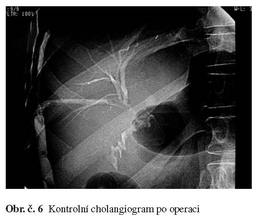

Založena hepatikojejunastomóza na segmentální žlučovody pravého jaterního laloku. Kontrolní cholangiografie po operaci zobrazuje patentní biliodigestivní anastomózu.